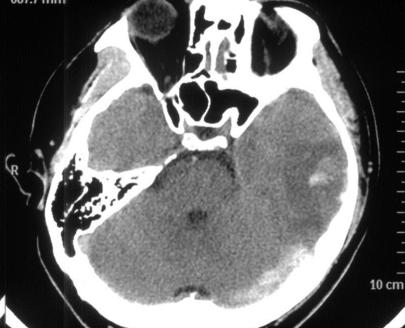

脑CT :左侧横窦条索征,左侧颞叶脑出血,见图1&5

图1

图5